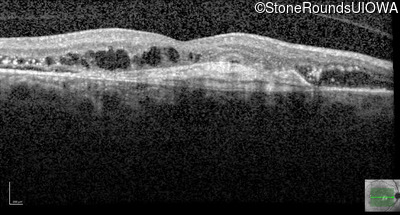

Optical Coherence Tomography - Right - 20/250

Exemplar / OCT Stack